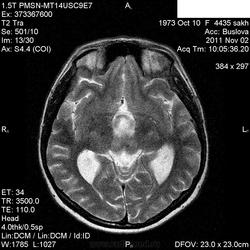

Случай моего коллеги.